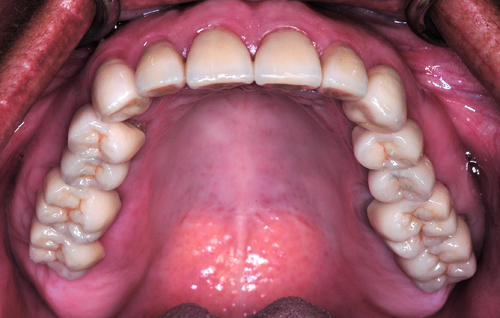

Osteotomías con Ultrasonido. Ensanchamiento Crestal. Mantenedores de Espacio Óseo. Oclusión. Paciente mujer, de 55 años derivada por colega para la realización de Rehabilitación Oral Integral . A la observación clínica se observan Fundas de Porcelana varias, algunos Pernos Muñones sin tallar, Empastes de Amalgama, y severos desgastes realizados en prótesis fija inferior derecha en el afán de lograr espacio interoclusal. También se observan múltiples desadaptaciones sin ajuste cavo superficial y filtraciones , así como áreas edéntulas con severas reabsorciones horizontales. Su estado periodontal está afectado en términos generales con Periodontitis generalizada observándose bolsas de entre 3 y 5 mm en distíntas áreas de la boca. Sus ATMs presentan clickings recíprocos y a la inspección corporal se observan codos y rodillas hiperlaxas, como así sus dedos pulgar y meñiques, lo que nos hace pensar en un cuadro de Hiperlaxitud Ligamentosa. Es clínicamente observable la enorme extrusión de los molares superiores debido a la carencia de antagonistas, lo que nos obligará a realizar una gran recorte de los tenidos dentarios y gingivales para lograr crear planos oclusales correctos. También las áreas edéntulas presentan un aspécto de filo de cuchillo, lo que supone crestas muy delgadas que confirmaremos con un Dentascan. Figura 1 Figura 2 Figura 3 Figura 4 Se toman impresiones y se realizan modelos de estudio que se montan en articulador semi ajustable, en Oclusión en Relación Céntrica (ORC). Figura 5 Figura 6 Figura 7 Figura 8 Figura 9 Figura 10 Observado el estudio radiográfico Dentascan se procede a operar las crestas óseas inferiores mediante técnica de Expansión de Crestas y Mantenedores de Espacio Óseo. (MOSTRAMOS SOLO EL PROCEDIMIENTO DEL LADO IZQUIERDO, HABIENDOSE REALIZADO SIMULTANEAMENTE TAMBIÉN EL DERECHO) Figura 11 Figura 12 Figura 13 Figura 14 Figura 15 Figura 16 Figura 17 Figura 18 Figura 19 Figura 20 Figura 21 Figura 22 Figura 23 Figura 24 Figura 25 Figura 26 Transcurridos seis meses procedemos a re intervenir para observar el hueso obtenido y reemplazar los mantenedores mediante implantes (conexión interna Triplo Ekckerman) de 4mm de diámetro por 13 mm de longitud, y chequeamos con una nueva OPM. Figura 27 Figura 28 Figura 29 Figura 30 Figura 31 Figura 32 Figura 33 Figura 34 Figura 35 Durante estos meses de espera de maduración del hueso obtenido entre los Mantenedores de Espacio Óseo, construimos en laboratorio un Encerado Progresivo de Diagnóstico y Trabajo por encerado de PKT.(Peter Kurt Thomas), mediante el cual se construyeron provisionales que cumplieron las correctas disclusiones correspondientes a una Oclusión Organizada. Figura 36 Figura 37 Figura 38 Iniciando ya la etapa protética, podemos observar en las FIGURAS 39 y 40, el recorte que realizaremos a las piezas sobre todo del lado derecho. Figura 39 Figura 40 (la línea azul inferior muestra el nivel de las fundas que porta el paciente-la línea roja el nivel de corte necesario, y la línea azul superior el nivel óseo) Tallamos entonces las piezas dentarias supero anteriores y las infero anteriores para establecer mediante los provisionales una nueva Guía Anterior. Figura 41 Figura 42 Figura 43 Figura 44 Figura 45 Figura 46 Figura 47 Observadas las correctas disclusiones procedemos a intervenir en los sectores posteriores, realizando primero gingivectomías mediante electrobisturí, y tallados programados según lo observado en las figuras 39 y 40. Figura 48 Figura 49 Figura 50 Figura 51 Figura 52 (OBSÉRVESE LA GANANCIA DE ESPACIO OBTENIDA ENTRE LAS FIG 50 Y 51) Una vez comprobada la salud de los tejidos periimplantarios, montamos los sectores posteriores de los provisionales. Figura 53 Figura 54 Figura 55 Figura 56 Figura 57 Figura 58 Figura 59 Figura 60 Tiempo después podemos observar en un control radiográfico la pérdida ósea del implante correspondiente a la pieza 46 por una probable carga anómala. Figura 61 Transcurridos seis meses durante los cuales se comprueba el correcto funcionamiento de la rehabilitación provisional considerando prioritariamente la Eficacia Masticatoria, la ausencia de síntomas dolorosos, la disminución de los clickings recíprocos, la buena función de la Guía anterior, etc.,procedemos a tomar impresiones definitivas para construir en primer término la Guía anterior en porcelana sobre circonio, y probarlas en boca. Figura 62 Figura 63 Figura 64 Figura 65 Figura 66 Figura 67 Figura 68 Corroborada la eficacia de la Guía Anterior Definitiva (que fue instalada y dejada durante dos semanas , con los posteriores en provisionales), procedemos a construir y probar en boca los circonios y la porcelana sobre circonio, observándose las Fuerzas de Deslizamiento de los inferiores sobre los Rebordes Marginales de los superiores por visión especular.(FIG 68) Figura 69 Figura 70 El tratamiento duró un año y medio, y llevamos controlándolo cuatro meses durante los cuales no se han observado remisión ninguna de los síntomas principales.

Obtenemos entonces un R.O.I. con una alineación tridimensional coherente entre arcadas antagonistas, cuatro niveles de oclusión y un Wilson adecuado.